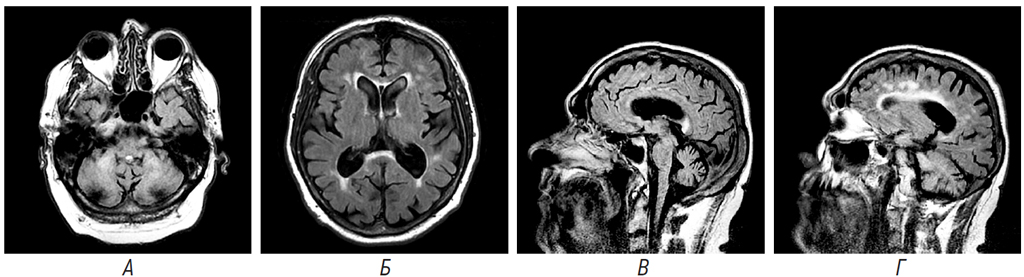

Результаты магнитно-резонансной томографии головного мозга пациента П. представлены на рисунке.

Рисунок. Результаты магнитно-резонансной томографии головного мозга пациента П., мужчина, 58 лет. А. Гиперинтенсивные очаги в области средних ножек мозжечка, FLAIR; Б. Гиперинтенсивный сигнал от валика мозолистого тела, Т2-ВИ; В. Гипотрофия мозжечка, гиперинтенсивный сигнал от валика мозолистого тела; Г. Перивентрикулярный лейкоареоз

Fig. 1. Results of magnetic resonance imaging of the brain of patient P., male, 58 years old. A. Hyperintensive foci in the region of the middle legs of the cerebellum, FLAIR; Б. Hyperintensive signal from the corpus callosum roller, T2-VI; B. Cerebellar hypotrophy, hyperintensive signal from the corpus callosum roller; Г. Periventricular leukoareosis